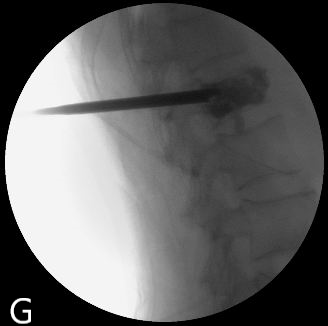

PVP是在影像引導(dǎo)下通過將穿刺針經(jīng)皮穿刺到病變椎體后向椎體內(nèi)注入骨水泥,以達到緩解腰背疼痛,增強椎體強度和穩(wěn)定性,防止塌陷,是部分恢復(fù)椎體高度的一種微創(chuàng)脊柱外科技術(shù)。PKP是在PVP的基礎(chǔ)上使用球囊擴張椎體的技術(shù)。

圖為:南通瑞慈醫(yī)院骨科PVP術(shù)中影像

這兩種術(shù)式均是針對老年人設(shè)計,具有創(chuàng)傷小,不需全身麻醉,術(shù)后恢復(fù)快等優(yōu)勢,病人術(shù)后第二天就能下床活動。南通瑞慈醫(yī)院骨科脊柱外科于2005年首次開展此項技術(shù),如今已形成平均每年150例手術(shù)量規(guī)模,幫助諸多老年患者擺脫了疾病困擾。